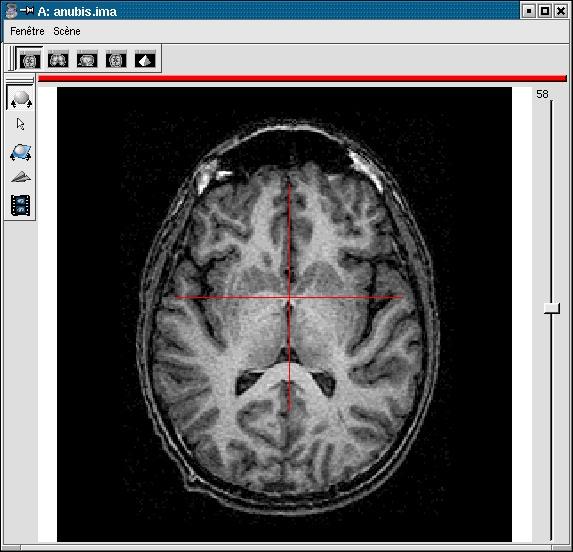

If your image is not spatially normalised, Anatomist will help you to click on the 3 or 4 points of interest.

- If the volume is not already visible, click on the edit button of one of the point parameters to have Anatomist display it

- Set the Anatomist view so as to see the point (use the slice slider) and click in it on the wished point.

- When the cursor position is good, click on the button of the 3D point in BrainVISA: the position is transfered from Anatomist to BrainVISA.

- If you are not happy with the position, you can restart the operation: click again on other points then on the parameter button to validate: a new position replaces the previous one in BrainVisa.

You have to select 3 points (you can use a sagittal slice if you prefer):

- Intersection of anterior commissure with interhemispheric plane;

- Intersection of posterior commissure with interhemispheric plane;

- Any point of the interhemispheric plane not aligned with the previous ones.

- Optionally, any point of the left hemisphere. Specifying this point is not mandatory, it is only useful to detect a possible orientation problem on the input image. Be careful, axial and coronal views in Anatomist are in radiological convention by default (left and right are flipped).

Posterior commissure: